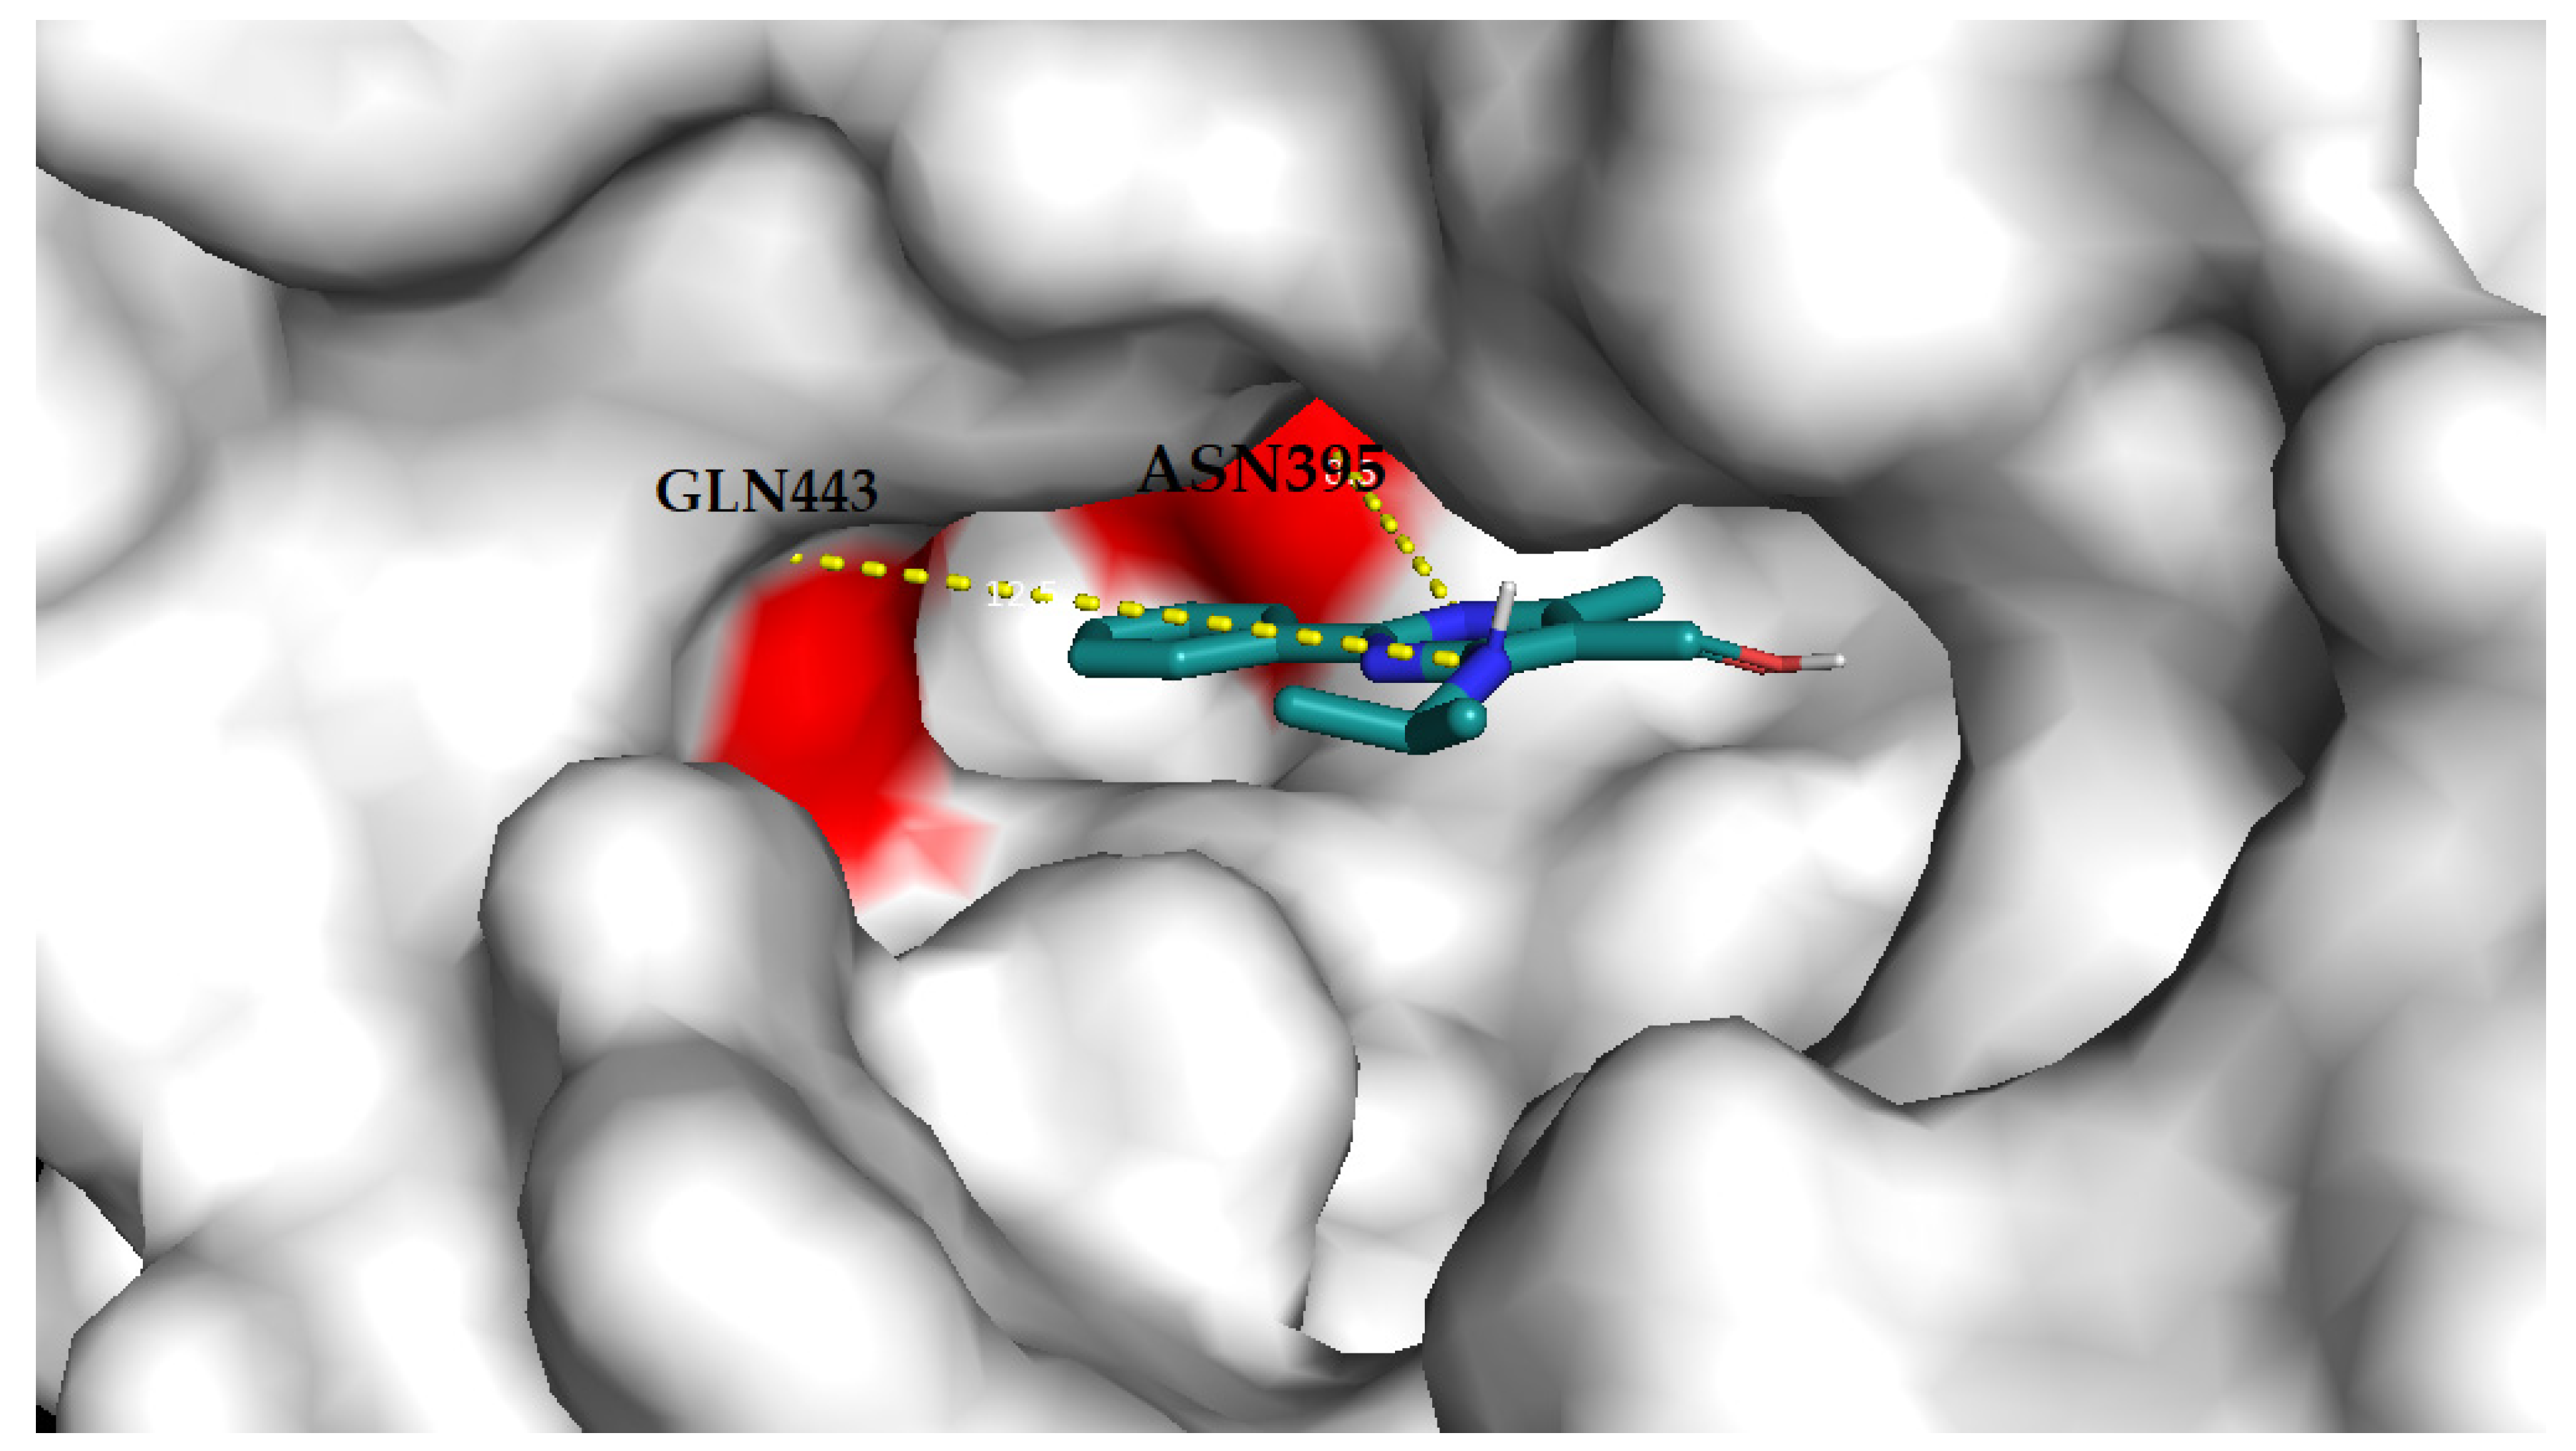

3.4.2. Molecular Docking Analysis

4. Discussion